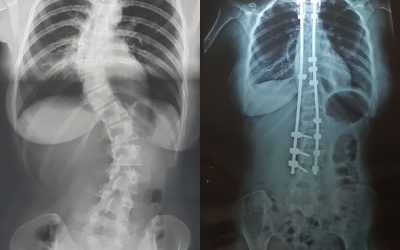

Arthrodèse et Grossesse.

Et oui, me revoilà avec une bonne nouvelle ! Un bébé grandit en moi depuis plusieurs mois maintenant. Ce début de grossesse, qui s’est relativement bien passé. J’avais quelques craintes concernant les maux de dos, les nausées et autres symptômes pas très...